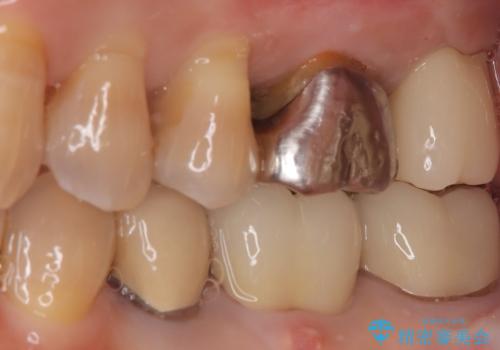

【根管治療】ズーンと痛い歯の治療。

- 奥歯付近がジーンと痛いことを主訴に来院されました。

左上7番の歯は、歯髄検査にて反応を示し、歯周ポケットはありませんでした。

親知らず抜歯を行い、痛みの変化や歯根吸収の有無を確認したのち、抜髄処置を行っています。

症状改善し、遠心の骨の回復も認めます。

バイオセラミックシーラーを使用して根管充填を行っています。